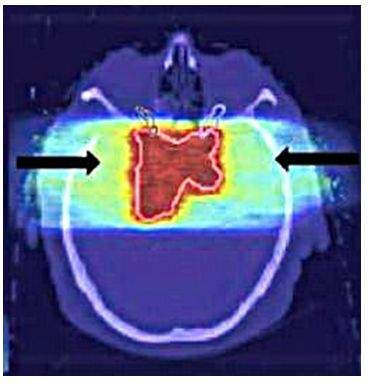

Abbildung 5: Eine CT-Aufnahme eines Gehirntumors (roter Bereich). Quelle: Mit freundlicher Genehmigung durch Katja Parodi und Walter Assmann: Haddronen gegen den Krebs, in Physik Journal 18(2019) Nr.6, Seite 39, Abb3.

Innenliegende Tumore wie in Abb. 5 werden oft mit der Strahlentherapie behandelt. Wie in diesem Fall liegt der Hirntumor etwa 13 cm unter Schädeloberfläche. Um den Tumor durch eine Energiezufuhr zerstören zu können, muss der Ionenstrahl genau präpariert werden.